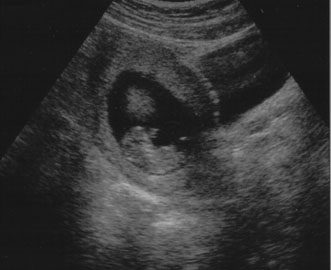

First trimester ultrasound may be performed transabdominally or transvaginally. Table 7 lists the components of a first trimester ultrasound. A crown–rump length, done between 7 and 13 weeks, can define a gestational age to within 5 days (Fig. 7).

Fig. 7. First trimester ultrasound showing crown–rump length.

Nuchal edema is an echo-free space between the skin line and the soft tissue overlying the cervical spine. Nuchal edema is caused by subcutaneous accumulation of fluid and has diverse etiology, including aneuploidies, cardiovascular and pulmonary defects, skeletal dysplasias, congenital infections, and hematologic and metabolic disorders. A nuchal translucency (NT) is obtained between 10 and 13 weeks' 6 days' gestational age (Fig. 8).31 A study at King's College Hospital in London found an NT of 3 mm was associated with a 4-times increase in the maternal age related risk for aneuploidy. An NT greater than 4 mm resulted in a 29 times increased risk for trisomies 21, 18, and 13. Additionally, with a 4 mm or more NT, there was a high incidence of other anomalies and poor prognosis, whereas with just 3 mm and a normal karyotype, the outcome was usually normal. Table 8 lists the disorders associated with an increased nuchal translucency thickness.

Fig. 8. Normal nuchal translucency of 0.19 cm at 11 weeks' gestation.